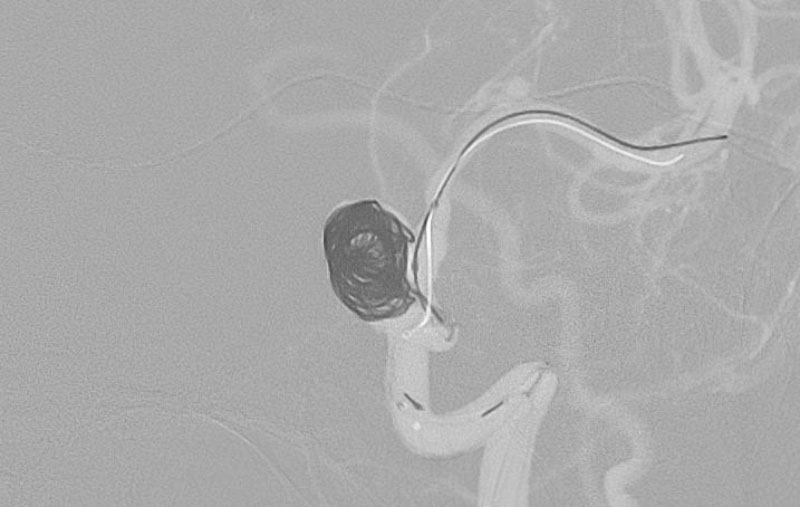

No.1592 手術前

No.1592 手術中

No.1592 手術後

'25年10月

くも膜下出血

右内頚動脈脳動脈瘤破裂

40代

救急外来